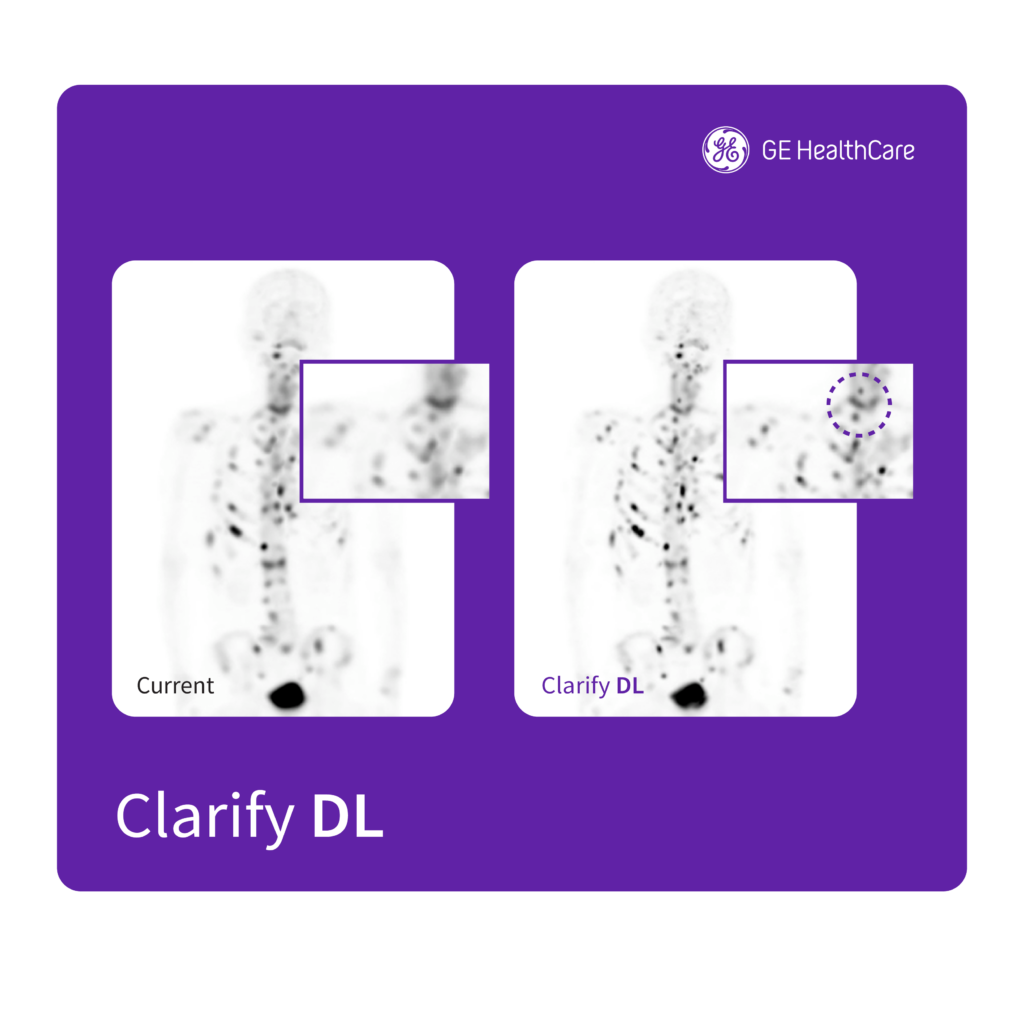

To assist clinicians in oncology, GE HealthCare’s Clarify DL[vi] nuclear medicine solution is designed to enhance bone SPECT image quality, an important factor in increasing diagnostic confidence.[vii] In a clinical evaluation, Clarify DL’s image resolution was rated as better in 98% of the exams.[viii] The AI-powered solution is designed to deliver clear, accurate, and effortless imaging – a stark contrast to today’s noise reduction techniques, that can lower noise at the expense of contrast and resolution. Clarify DL is designed for use with GE HealthCare’s StarGuide SPECT/CT system.

[vi] Clarify DL is CE marked as part of Xeleris V. 510(k) pending at the US FDA. Not available for sale in the United States.

[vii] Clarify DL improves dual head cameras’ image quality performance measured by Structures Similarity (SSIM) – up to 8% improvement, Mean Squared Error (MSE) up to 76% improvement, and Peak Signal-to-Noise Ratio (PSNR) – up to 18% improvement, as compared to GE bone SPECT factory reconstruction presets.* *Demonstrated using digital phantom simulations with inserted lesions of known size, location, and contrast, for AC and NC images.

[viii] As demonstrated in clinical evaluation in which 127 exams were rated by total of 9 physicians. Each exam was reconstructed with both Clarify DL and the existing factory reconstruction preset and evaluated by 3 of the physicians.